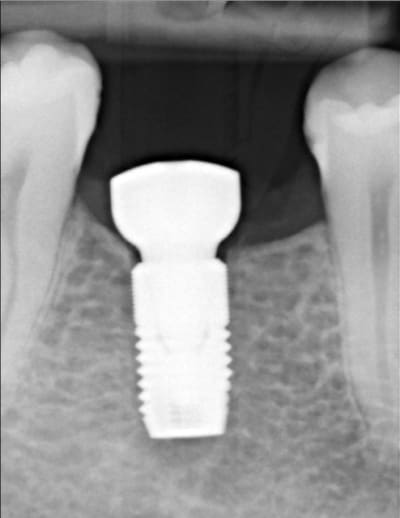

Bon je m'y colle, c'est pas le même niveau qu'olivier, mais ce sujet étant censé être pour les débutants je poste.

Patient 26 ans, à qui il manque 46, 25 et 26.

Pour l'instant je vous propose la partie préparation et mise en place de l'implant en 46, la suite peut être bientôt.

Dans l'ordre si le site veut bien, wax-up ( cirage pour céramik ;) ) , guide radio, et scan.

Photos pré-op, indicateur de direction en place et post-op.

Il s'agit d'un implant astra osseospeed de 5 mm de diamètre et 9 de long.

Prothèse prévue à 6 semaines.

puisque tu veux de la critique, impec (juste que je l'aurais mis à peine, mais vraiment à peine moins infra-osseux)

c'est à cause du profil de la crête, en fait l'implant est juxta-osseux en vestibulaire, par contre moi je le trouve ( légèrement ) trop distal.